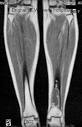

El adamantinoma aparece como una lesión lítica, excéntrica y circunscrita en radiografías simples. La corteza anterior de la tibia es el lugar más comúnmente afectado. Usualmente, la lesión tiene varios defectos líticos separados por hueso esclerótico lo cual le confiere apariencia de burbujas. Hay pérdida cortical pero poca reacción periosteal. La lesión puede llegar a atravesar la corteza y extenderse al tejido blando. Puede haber múltiples lesiones junto a tejido normal. Estudios de resonancia nuclear magnética (RNM) ayudan a determinar el grado de envolvimiento extraóseo e intraóseo. El diagnostico diferencial radiológico incluye displasia osteofibrosa, displasia fibrosa, quiste óseo aneurismático (QOA), fibroma condromixoide y condrosarcoma.